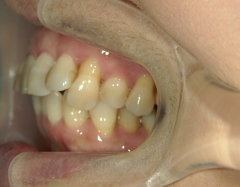

矯正歯科 治療前